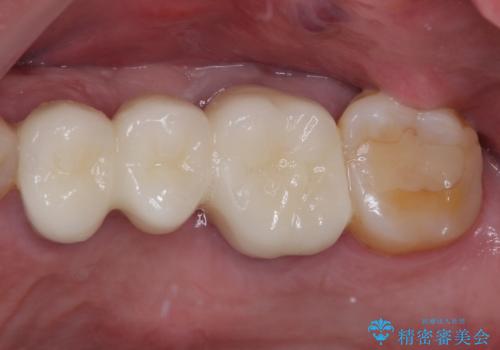

破折した歯を抜去し、インプラントによる補綴を行うこととしました。

銀歯の下のむし歯については、優先度の高い方からセラミッククラウンなどで治療していくこととしました。

治療開始時は右上奥歯と前歯のみが気になっていたのですが、その後下顎左右の奥歯に強い痛みや銀歯の脱離などが頻発し、問題のあるところは全て治療を行うこととしました。